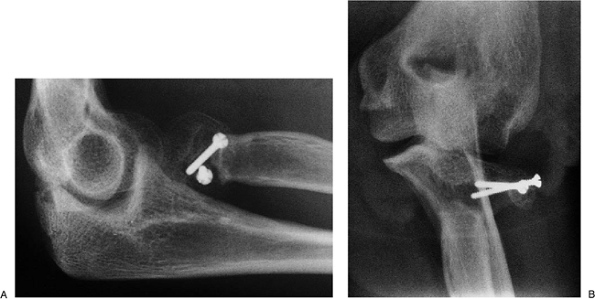

radial head and elbow dislocation. The effort to fix the radial head

was unsuccessful and the medial ulnar collateral ligament did not heal (Fig. 5-26).

Reconstruction with the radial head implant and tendon graft

reconstruction of the MCL were successful and the patient has minimal

discomfort or evidence of instability (Fig. 5-27).

Figure 5-26.

A 30-year-old physician underwent reduction and fixation of type III radial head fracture with concurrent elbow dislocation. The fracture went to a nonunion (A) and the medial collateral ligament failed to heal (B). |

|

Figure 5-27. Treatment with implant and MCL reconstruction. The implant is well positioned and the elbow is stable (A,B). At 4 weeks the patient has excellent motion and stability (C).